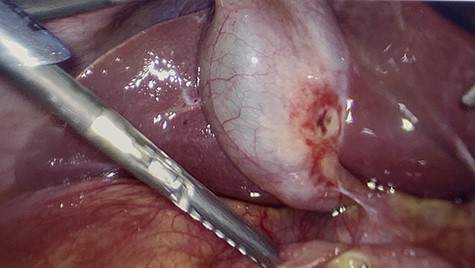

All of the standard preoperative measures were taken and the patient was prepped and draped for laparoscopic cholecystectomy. Ports were placed in a typical fashion for this operation, with A 12 mm Hasson trocar placed in a supraumbilical position, and 5 mm trocars placed in the epigastrium and RUQ x2. Upon insertion of the laparoscope, the uterus was still large in the pelvis and there was a small amount of bloody fluid in the abdomen. The fundus of the gallbladder was grasped and retracted cephalad. With this maneuver it appeared that the duodenum had fused itself to the infundibulum of the gallbladder. Upon gently peeling the duodenum off of the gallbladder, it became obvious that there was a perforated duodenal in the first portion of the anterior duodenum and had been the gallbladder that sealed the perforation (Figs 4–6). The gallbladder showed signs of erosion at the site where it patched the duodenum as well (Fig. 6). At this time we proceeded with laparoscopic cholecystectomy first, prior to addressing the duodenum. Once successfully completed with the cholecystectomy, we performed a laparoscopic graham patch with our existing ports, which can be seen in Fig. 7. A #10 flat JP was inserted in the region of the graham patch. The abdomen was irrigated and then suctioned clean. The repair was confirmed by placing underwater with the second portion of the duodenum compressed, while anesthesia insufflated the stomach/duodenum through an OG tube. The patient tolerated the operation well, extubated, and transported to recovery.

The gallbladder had been gently resected from the duodenum revealing a nonperforated ulceration where it had been patching the duodenal ulcer.